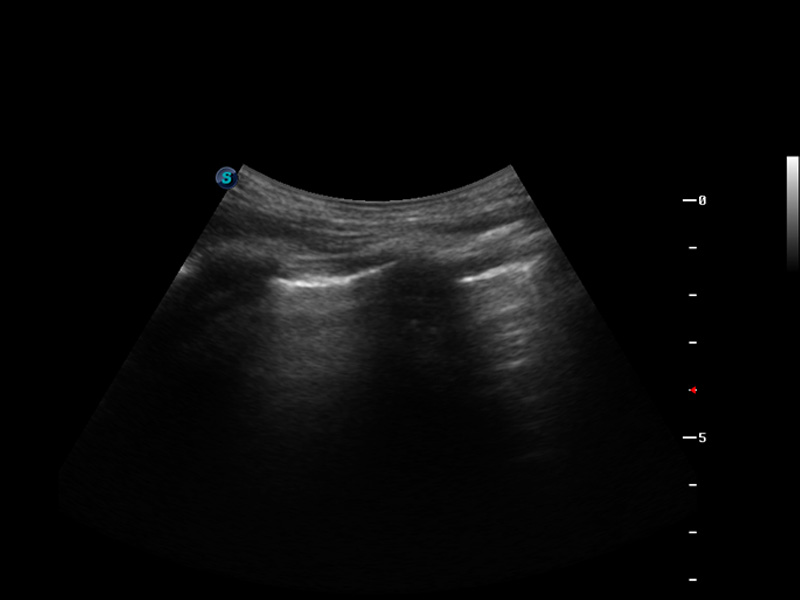

S9便携式彩色多普勒超声诊断仪是竞技宝(JJB)官方网站研发的高端便携彩超设备,外观设计新颖、产品性能卓越。S9在便携超声领域采用了突破传统的触摸屏交互设计,并以先进的软件硬件技术和设计理念,为您带来清晰的图像质量、稳定的工作性能和便捷的操作体验。

μ-Scan微米成像